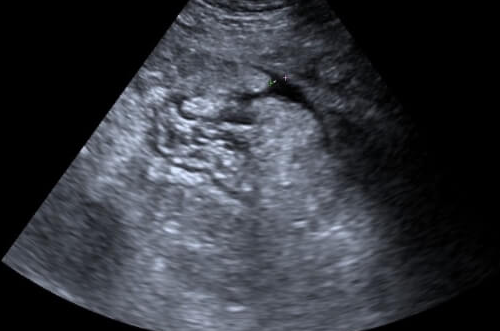

不建议孕妇服用护肝片,女性朋友体内的激素会在孕期发生变化。最好什么药都不要吃,因为是三分毒,可能对肚子里的胎儿有害,而且护肝片成分多,可能对什么成分都不过敏,造成不好的现象。所以主要是为了孕期保护胎儿。可以多吃新鲜蔬菜水果,更好的保护胎儿。